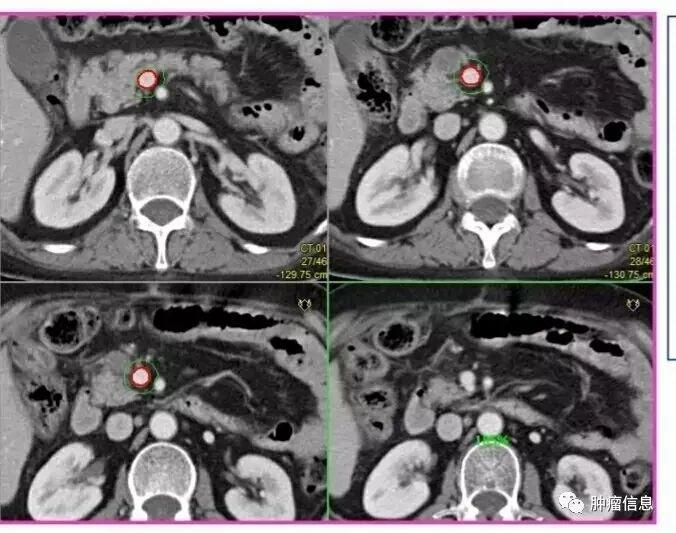

No.16腹主动脉旁淋巴结

上界:腹腔干上缘下界:L3下缘(肠系膜下动脉上缘)